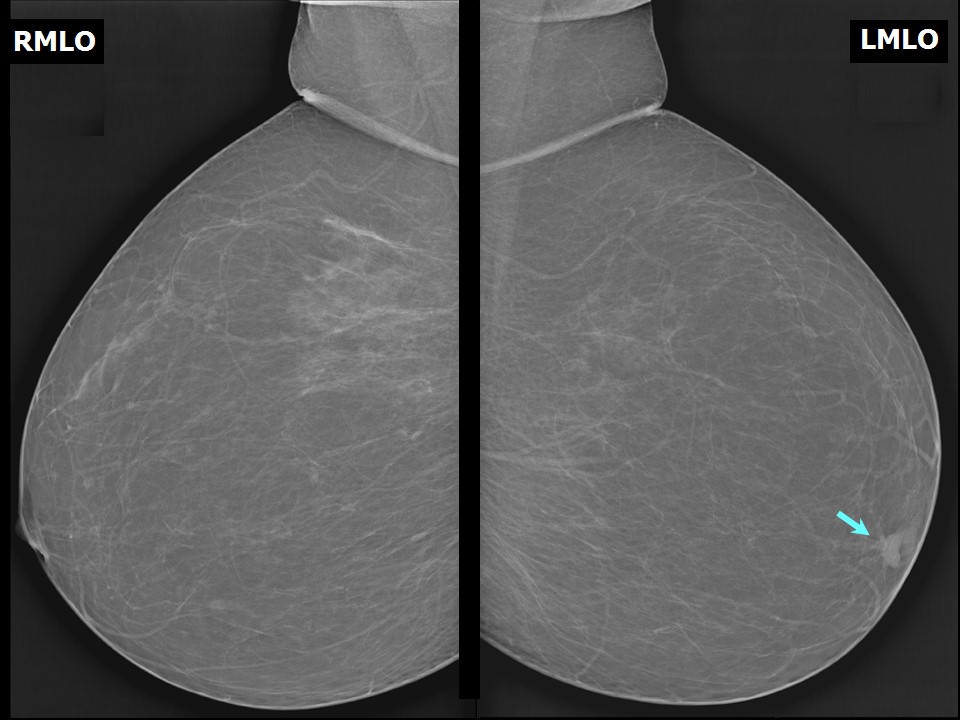

Basics

of

Interpreting

Mammogams